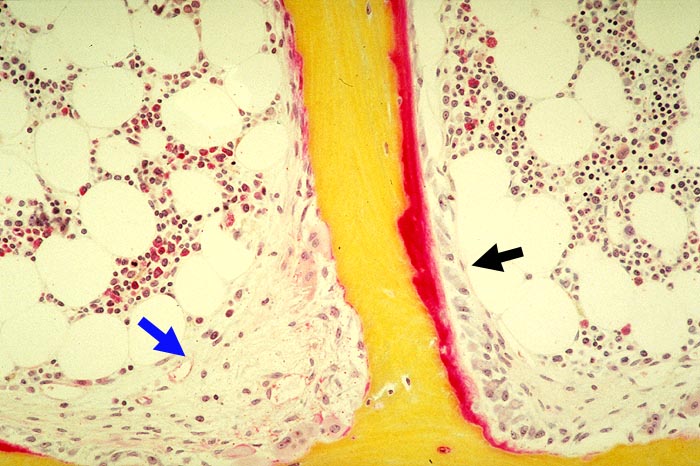

Renale Osteopathie

Knochen, Knorpel, Gelenke

Knochen

Knochen (Wirbelkörper und Discus intervertebralis)